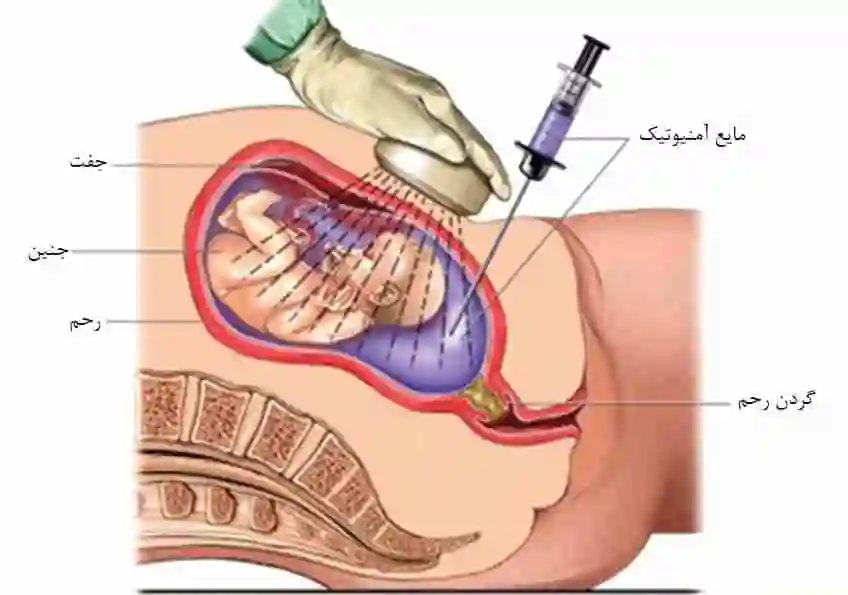

کدام بارداری ها نیاز به انجام آمنیوسنتز دارند؟

آمنیوسنتز یکی از تستهای غربالگری قبل از بارداری می باشد که یک پروسیجر هم تشخیصی هم درمانی است. به کمک سونوگرافی&